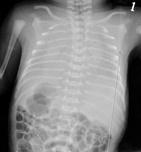

新生兒呼吸窘迫綜合征

• 新生兒呼吸窘迫綜合征